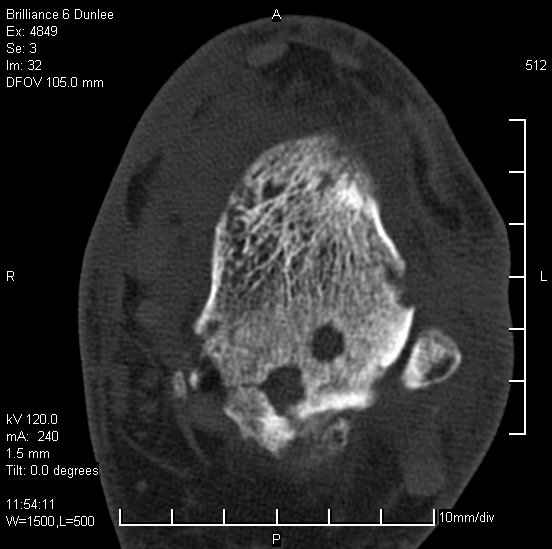

Асептический некроз таранной кости.

На лечении находится пациент 35 лет. Травма в сентябре 2008 г.- открытый вывих таранной кости

В день травмы ПХО, вправление вывиха, трансартикулярная фиксация. Рана зажила первично. С января нагрузка на конечность. С конца апреля- болевой синдром. На рентгенограммах и КТ признаки ас. некроза таранной кости, артроз подтаранного и голеностопного суставов.